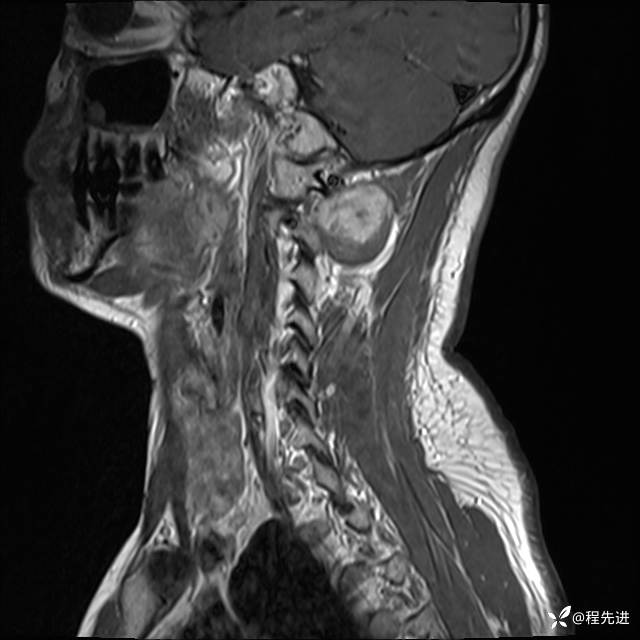

MRI平扫+增强:

T2: